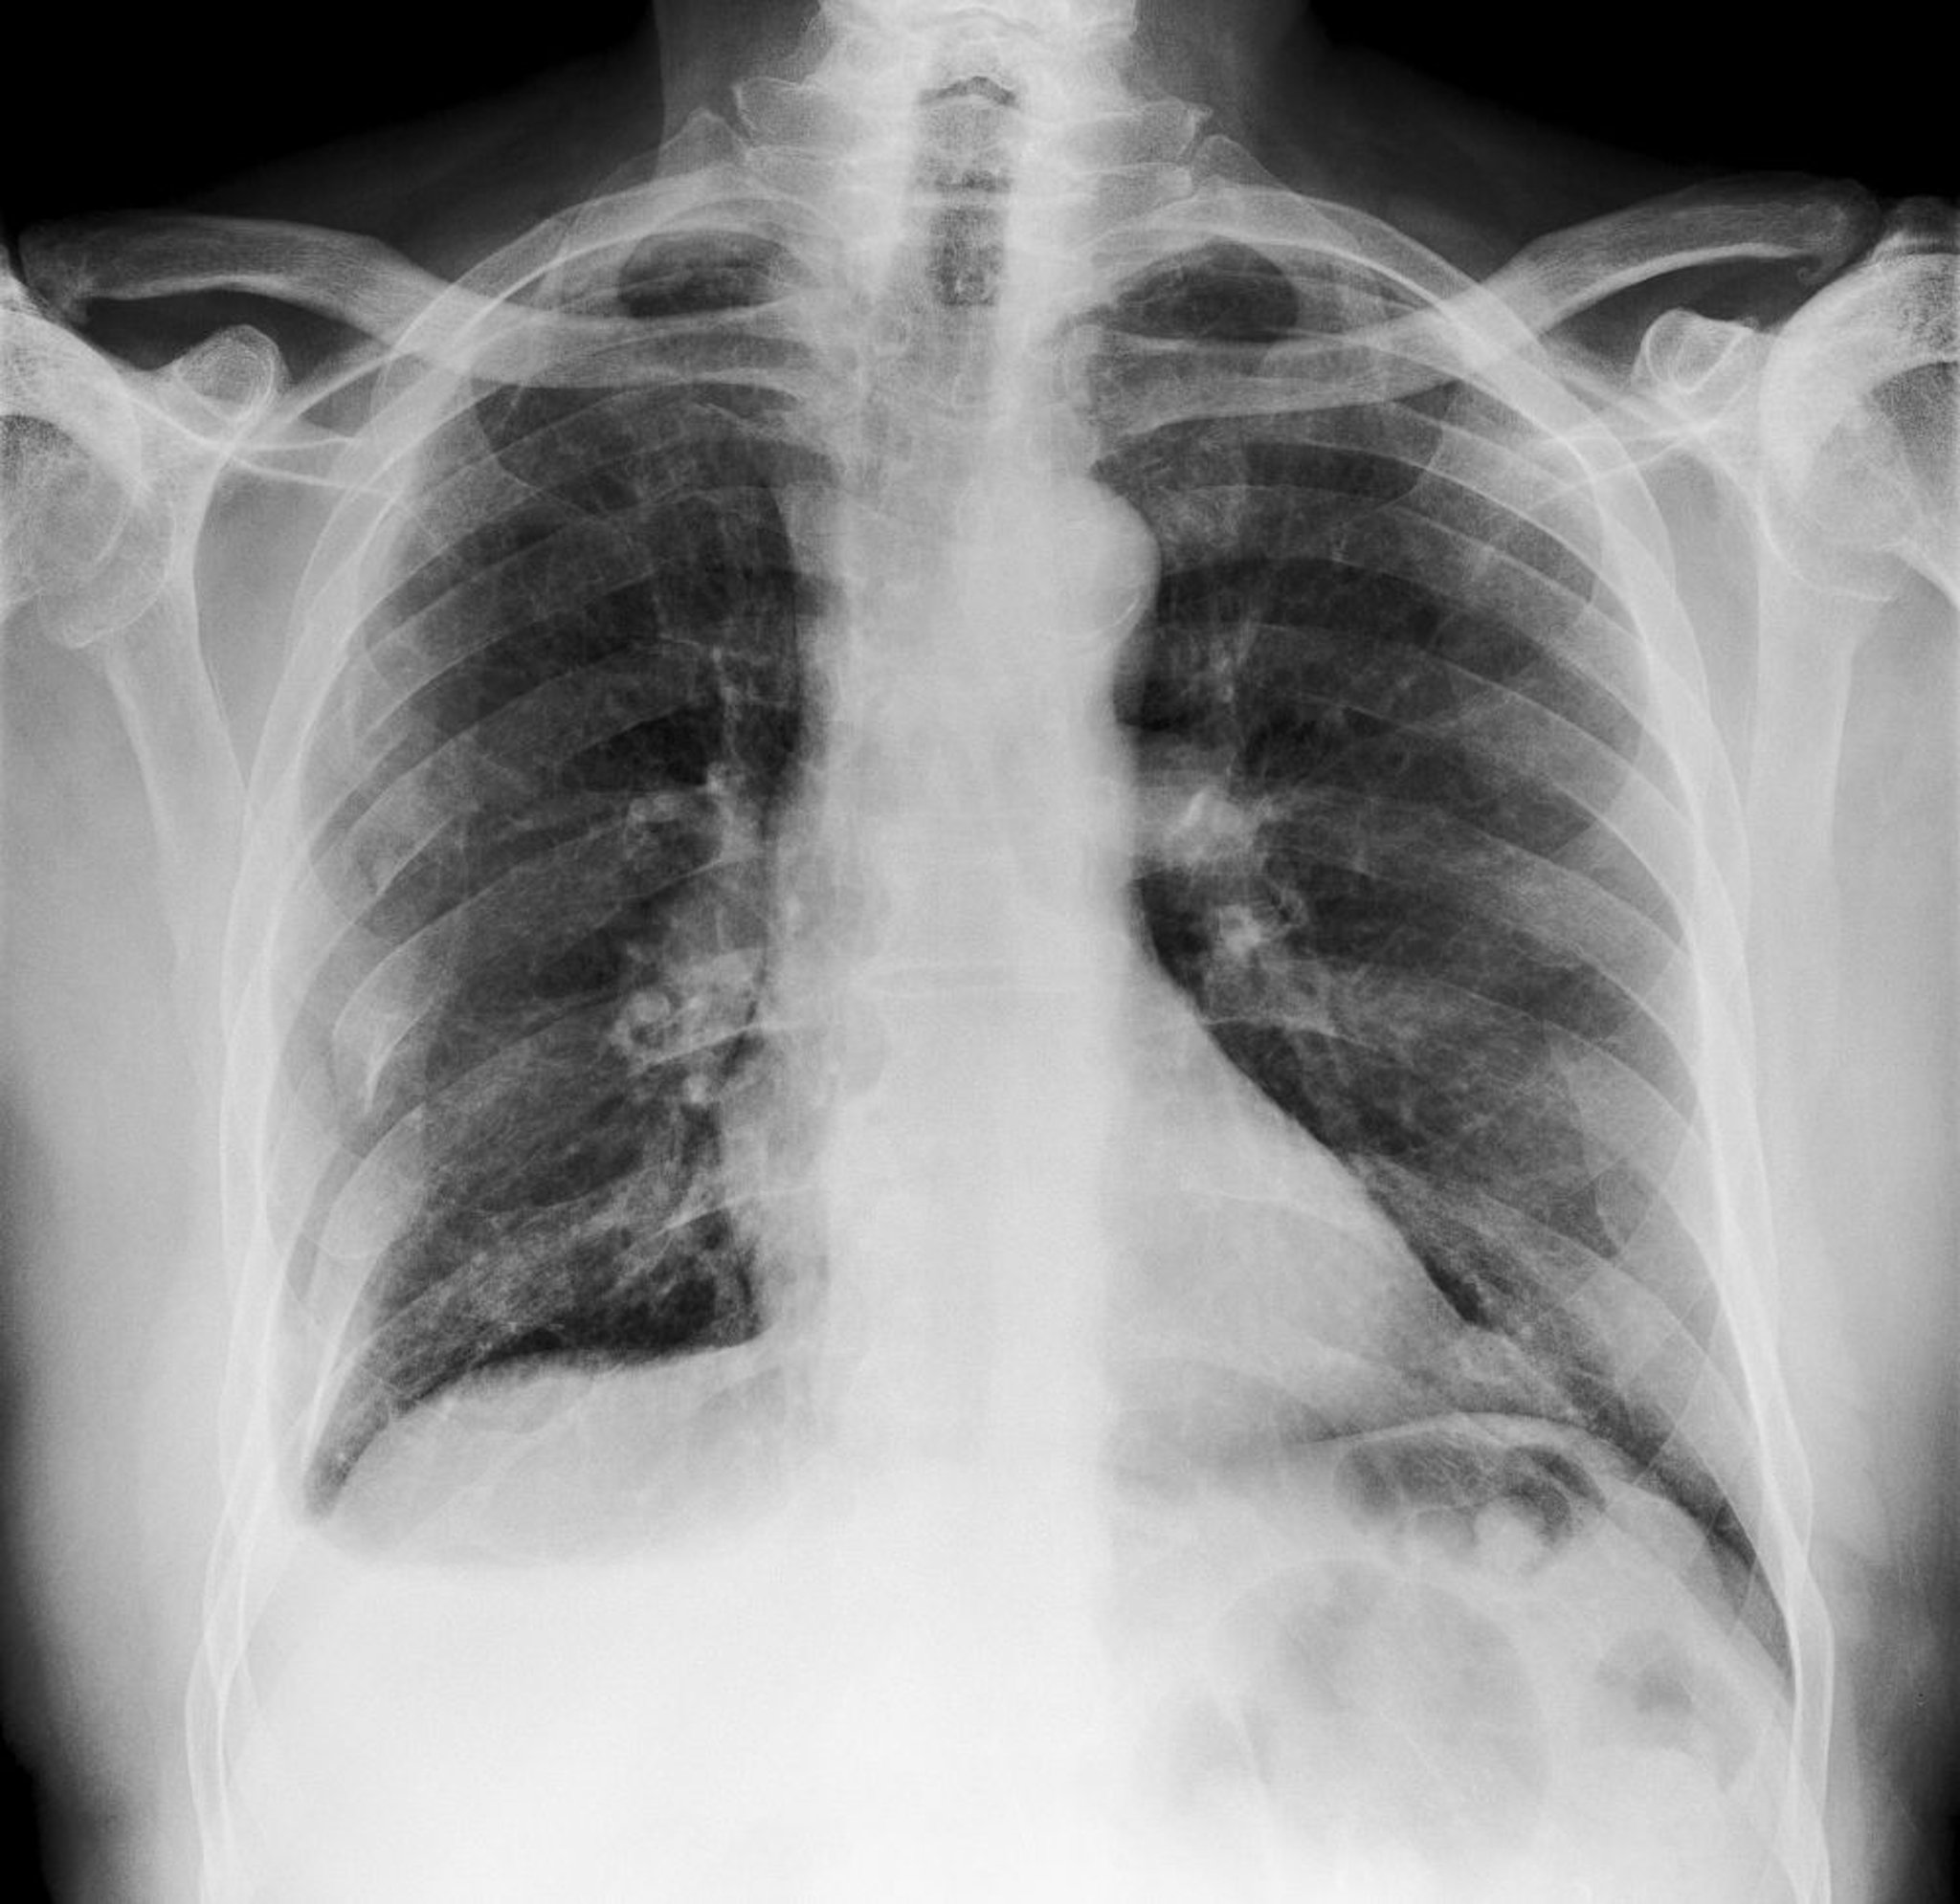

この胸部X線写真には,右肋骨に生じた多発骨折が写っている(写真では左側)。